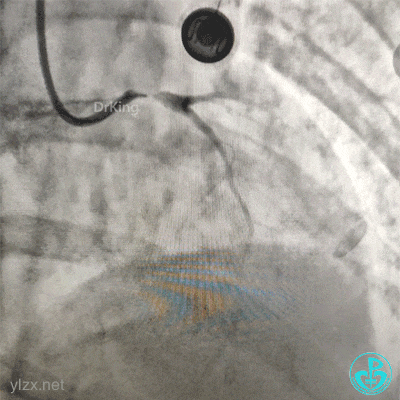

下午18:00复查超声:

凌晨03:00复查超声:

患者于凌晨02:20左右突发心脏骤停,心电监护呈等电位线。经抢救1小时无效死亡。

1. 心包积液的原因是什么:冠脉穿孔?急性心肌梗死早期心包炎?最后出现较大量的心包积液是心脏破裂吗?

2. 死亡原因:循环崩溃?心包填塞?机械并发症?